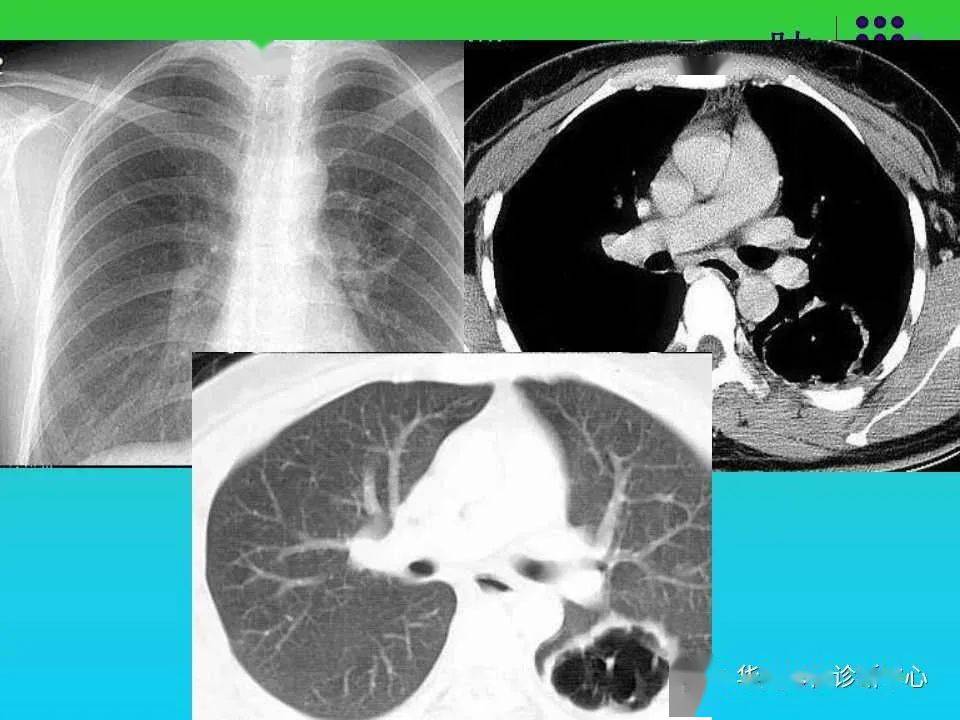

肺空洞性病变和囊性病变的ct诊断